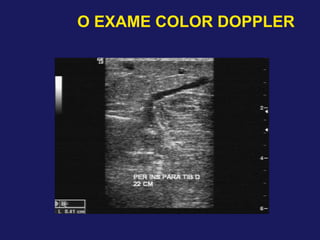

– Dimensões das veias perfurantes

– Ø > 3,5 mm – 90% de refluxo significativo – Sandri et al 1999